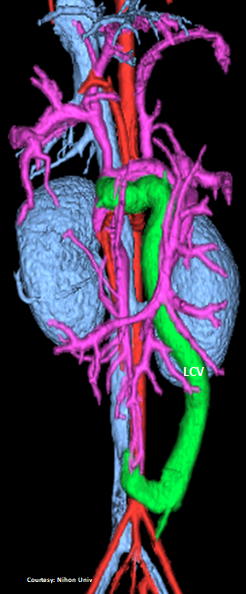

(GSV present)

“LGC +RGV +SGV”

Left Gastro-Caval Shunt with Right Gastric Vein and Short Gastric Vein contributions

Courtesy: Nihon Univ

WEISSE 2022